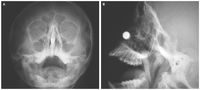

Hasil rontgen menunjukkan bahwa magnet menjepit bagian dinding hidung yang memisahkan lubang hidung kiri dengan kanan. Awalnya dokter mencoba memisahkan kedua magnet tersebut dari luar namun gagal.

Kondisi magnet di dalam hidung sang anak dari depan (kiri) dan samping (kanan). Foto: Live Science/The New England Journal of Medicine |

Kondisi magnet di dalam hidung sang anak dari depan (kiri) dan samping (kanan). Foto: Live Science/The New England Journal of Medicine